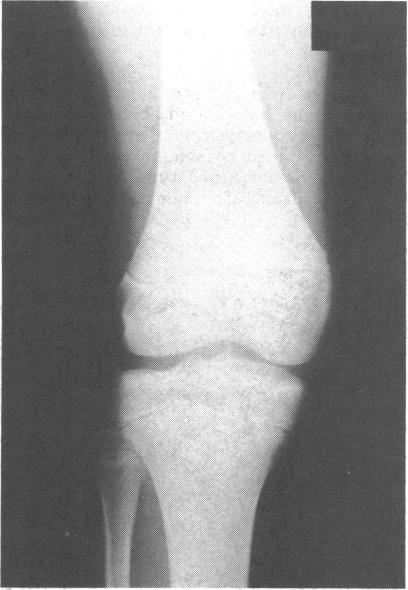

累及髌骨体的撕脱性骨折。

Avulsion fracture involving the body of the patella.

A report on an unusual transverse fracture through the body of the patella in a 13 year old high jumper is presented. The clinic features and treatment of the more usual avulsion injury of the patella is discussed.

摘要

本文报告了一例13岁跳高运动员髌骨体部罕见的横行骨折。文中讨论了更为常见的髌骨撕脱伤的临床特征及治疗方法。